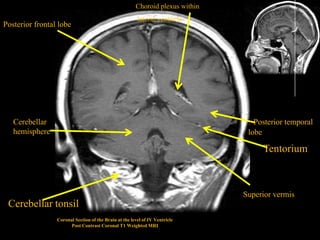

Choroid plexus within

lateral ventricle

Posterior frontal lobe

Cerebellar                                                                   . Posterior temporal

hemisphere                                                                   lobe

Tentorium

Superior vermis

Cerebellar tonsil

Coronal Section of the Brain at the level of IV Ventricle

Post Contrast Coronal T1 Weighted MRI

Choroid plexus within lateral ventricle Posterior frontal lobe Cerebellar . Posterior temporal hemisphere lobe Tentorium Superior vermis Cerebellar tonsil Coronal Section of the Brain at the level of IV Ventricle Post Contrast Coronal T1 Weighted MRI